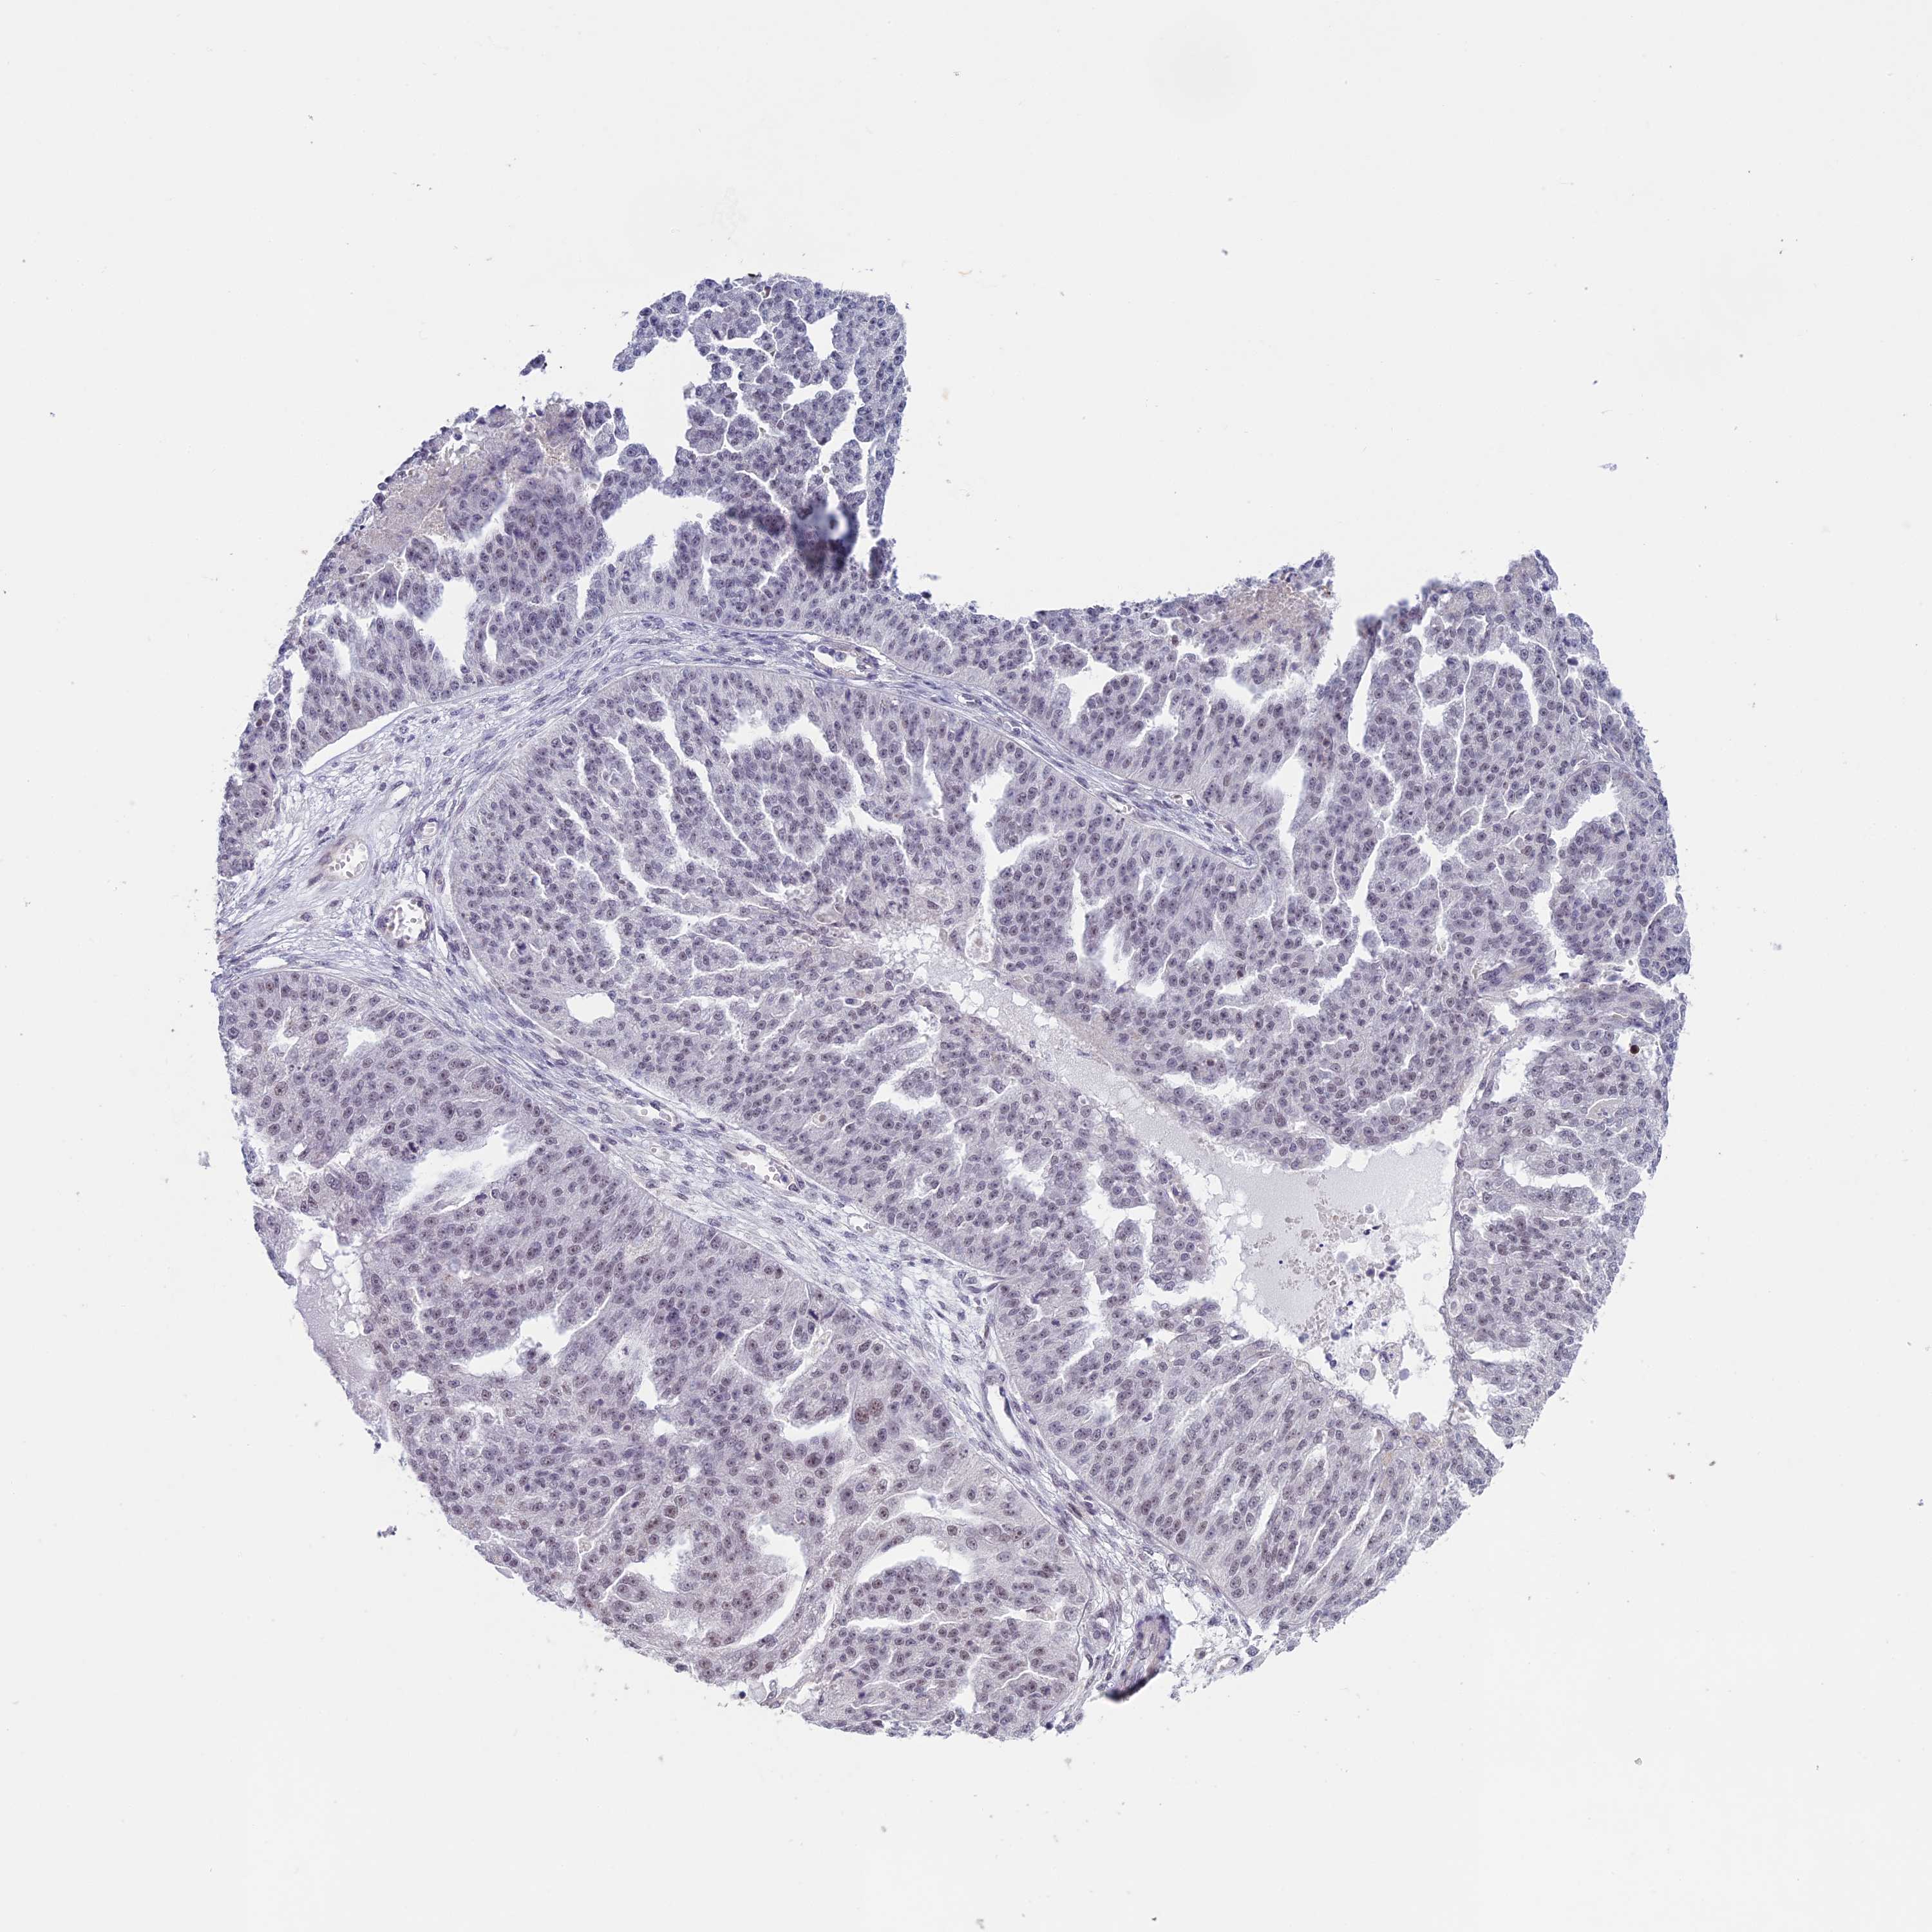

OVARIAN CANCER - Protein expressioni

A mouse-over function shows sample information and annotation data. Click on an image to view it in a full screen mode. Samples can be filtered based on level of antibody staining by selecting one or several of the following categories: high, medium, low and not detected. The assay and annotation is described here.

Note that samples used for immunohistochemistry by the Human Protein Atlas do not correspond to samples in the TCGA dataset.

Antibody stainingi

Antibody staining in the annotated cell types in the current human tissue is reported as not detected, low, medium, or high, based on conventional immunohistochemistry profiling in selected tissues. This score is based on the combination of the staining intensity and fraction of stained cells.

Each image is clickable and will lead to virtual microscopy that enables deeper exploration of all samples and also displays staining intensity scores, fraction scores and subcellular localization as well as patient and tissue information for each sample.

Antibody HPA042360

Staining

High

Medium

Low

Not detected

Intensity

Strong

Moderate

Weak

Negative

Quantity

>75%

75%-25%

<25%

None

Location

Nuclear

Cytoplasmic/membranous

Cytoplasmic/membranous,nuclear

Cystadenocarcinoma, serous, NOS

Carcinoma, endometroid

Cystadenocarcinoma, mucinous, NOS

Carcinoma, NOS